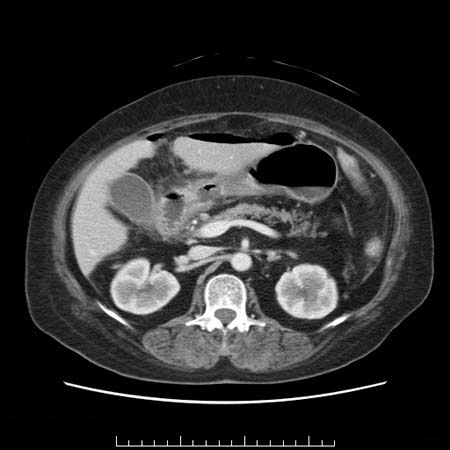

57歳 女性